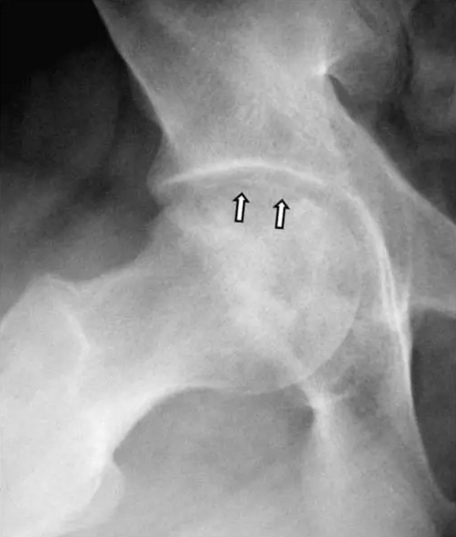

在死骨和活骨之间的界面处的小梁骨,由于机械损伤可能加剧无血管坏死(AVN)。在软骨下区域,这种微裂缝不愈合,因为它们发生在死骨区域内。 微裂缝的进展导致弥漫性软骨下骨折,在放射学上看作新月形征(见下面第一图)。在软骨下骨折和进行性加重之后,关节软骨发生塌陷(参见下面的第二至第五张图)。继续骨折、坏死和进一步加重,可进展为退行性关节疾病(DJD)和关节溶解(参见下面的第二张图片和最后2张图片)。

股骨头缺血坏死

该患者的缺血坏死显示新月标志,表明软骨下骨折。 一旦出现这种迹象,治疗性干预就不太可能阻止疾病的进展。